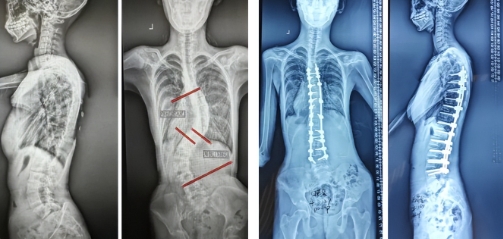

16岁的高中生小林,最早发现脊柱侧弯时Cobb角44°,未接受手术治疗,通过佩戴支具及理疗等保守治疗,佩戴支具近2年,侧弯角度增加到58°,患者及家属仍无法接受手术, 住院时Cobb角高达88°,通过手术矫正后,患者脊柱侧弯明显改善,且身高增长6厘米,现已顺利返回学校正常学习生活。